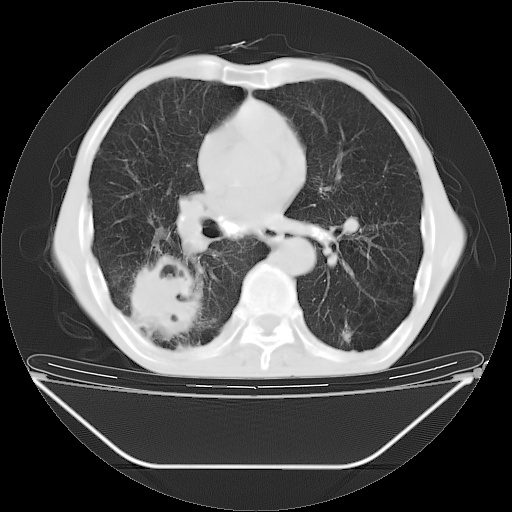

以下是引用随光逐影在2008-8-25 22:03:00的发言:[br]1)考虑右肺下叶周围性肺癌并肺内转移,腰椎附件转移。2)左上肺结核(结核球形成)。3)双肺肺气肿(多发肺大泡形成)。4)双肺门区及纵隔内多发淋巴结钙化。

以下是引用zsl6918在2008-8-25 21:55:00的发言:[br]符合右肺周围性肺癌并肺内转移,左肺结核球。双肺肺气肿。腰椎附件转移。

以下是引用qc80012345在2008-8-26 6:14:00的发言:[br]符合右肺周围性肺癌并肺内转移,左肺结核球。双肺肺气肿。腰椎附件转移。